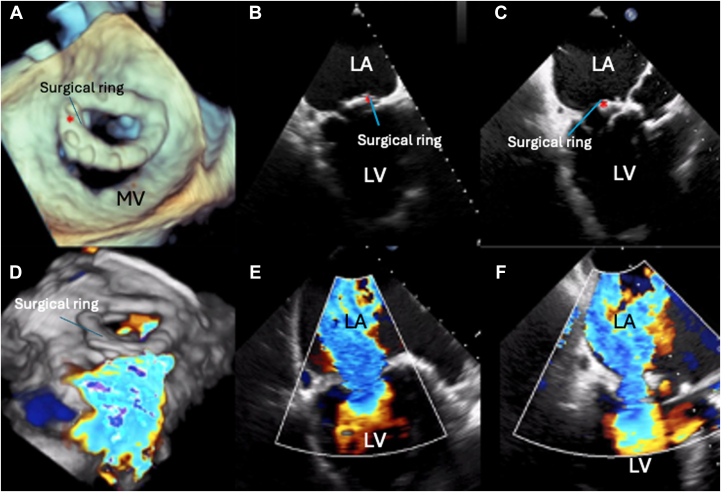

A 79-year-old man with prior surgical mitral valve repair using a 32-mm Edwards ring was admitted for worsening heart failure (NYHA functional class III/IV). Transesophageal echocardiography (TEE) revealed wide dehiscence of the mitral ring from the anterolateral to the posteroseptal commissure, with severe MR secondary to posterior leaflet restriction (Figure 1, Video 1).

Preprocedural Transesophageal Echocardiogram

(A) Three-dimensional transesophageal echocardiography reconstruction of the MV showing posterior dehiscence of the surgical ring (red asterisk), creating an ample orifice between the surgical ring and the mitral annulus. The detached surgical ring (red asterisk) and dehiscence are shown in the 2-chamber view (B) and the long-axis view (C). Massive mitral regurgitation is demonstrated in a 3-dimensional color Doppler reconstruction (D) and with color Doppler imaging in the 2-chamber (E) and long-axis (F) views. LA = left atrium; LV = left ventricle; MV = mitral valve; Surgical ring = ring.